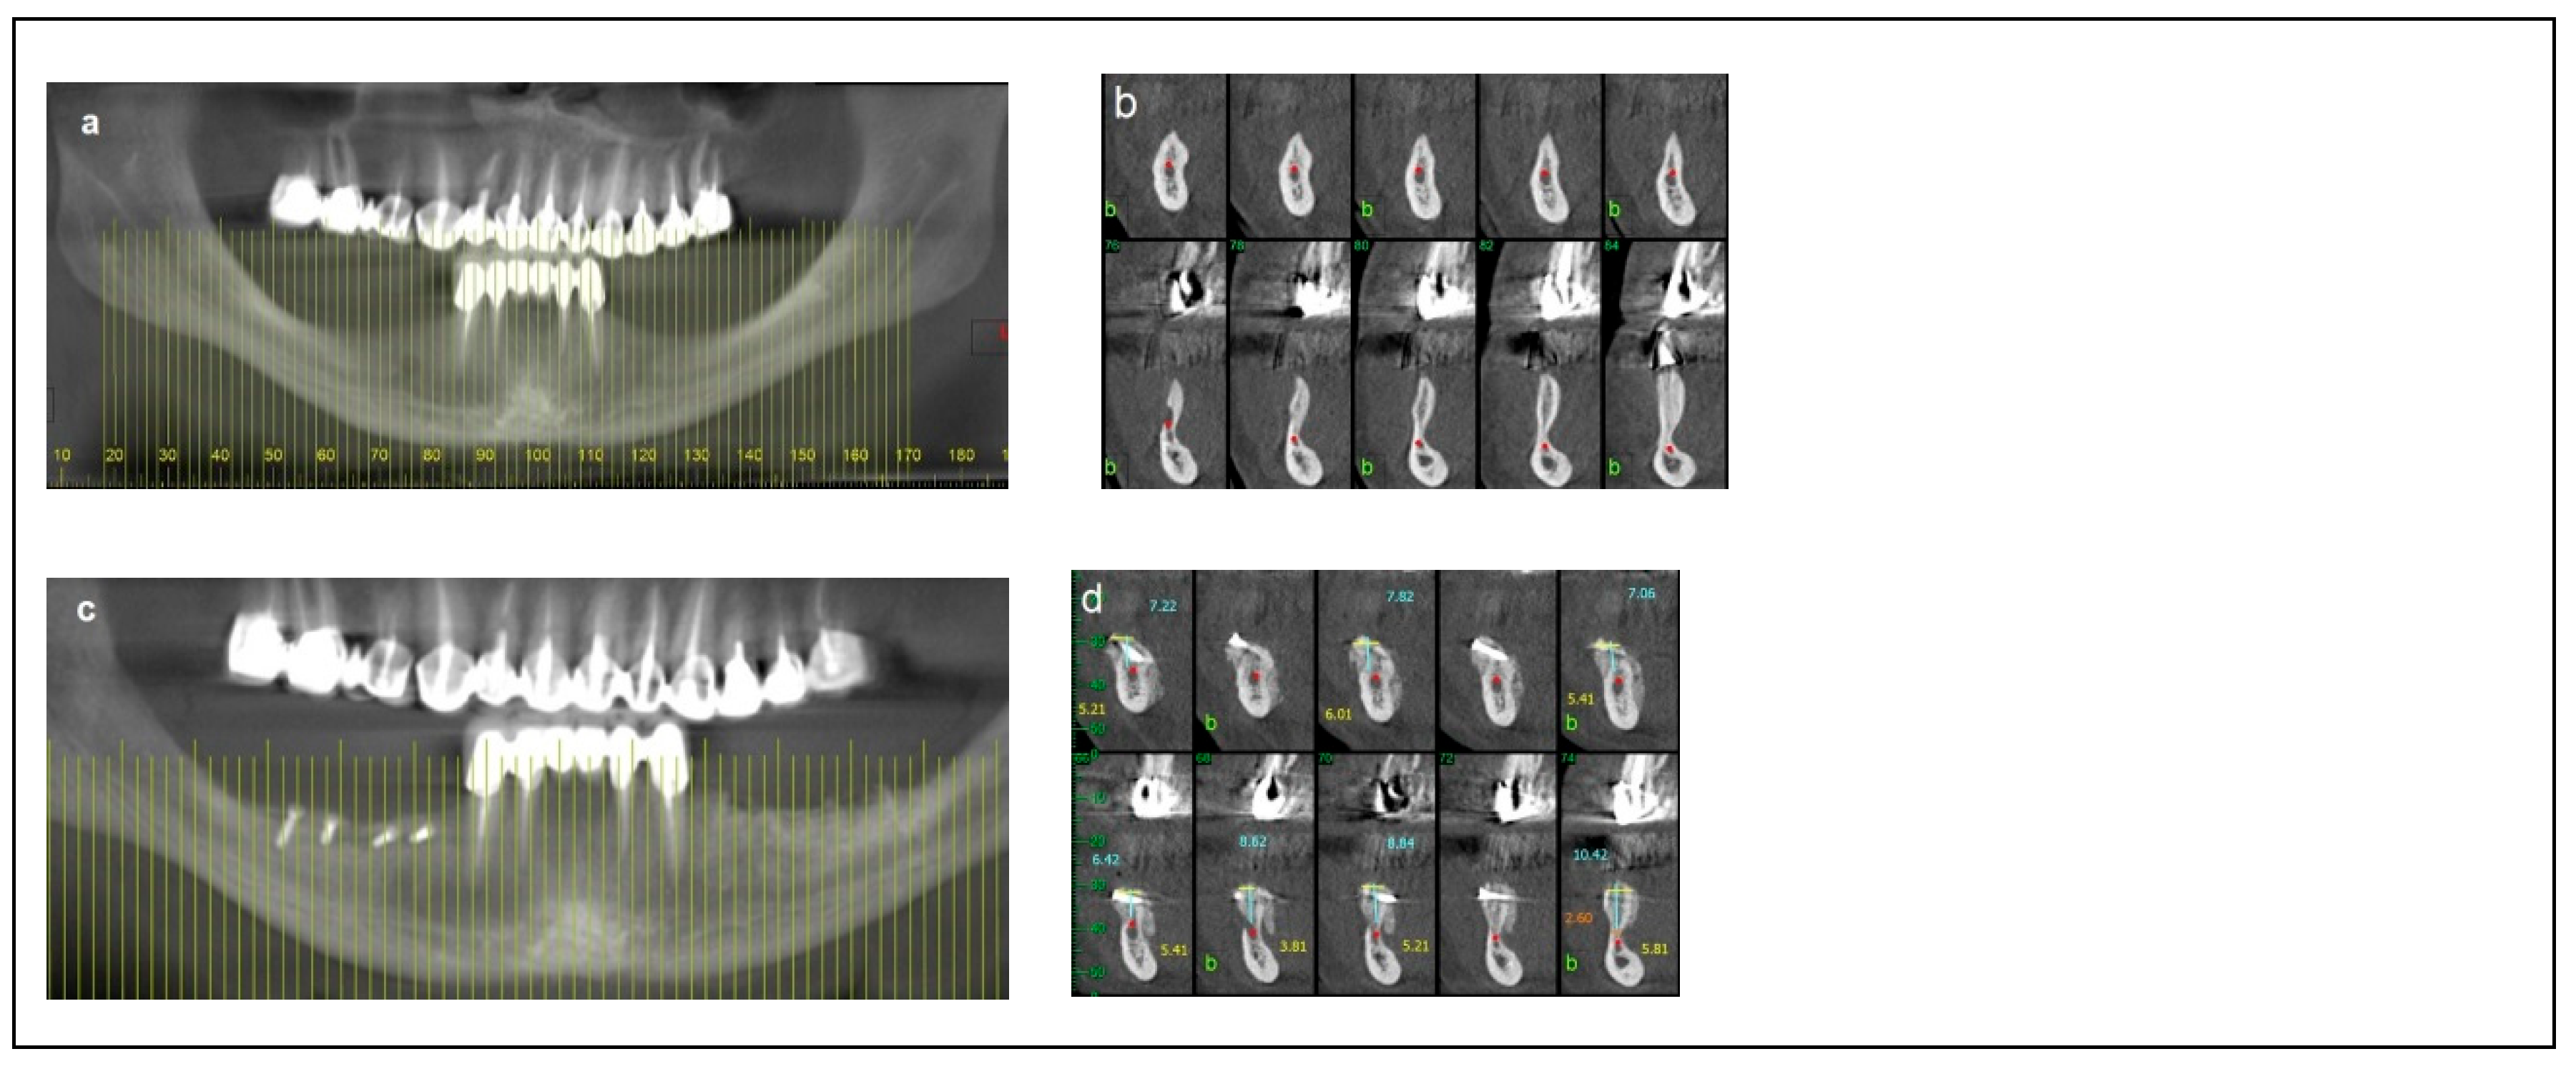

2. Materials and Methods

2.1. Category 1

2.2. Category 2

2.3. Category 3

2.4. Category 4